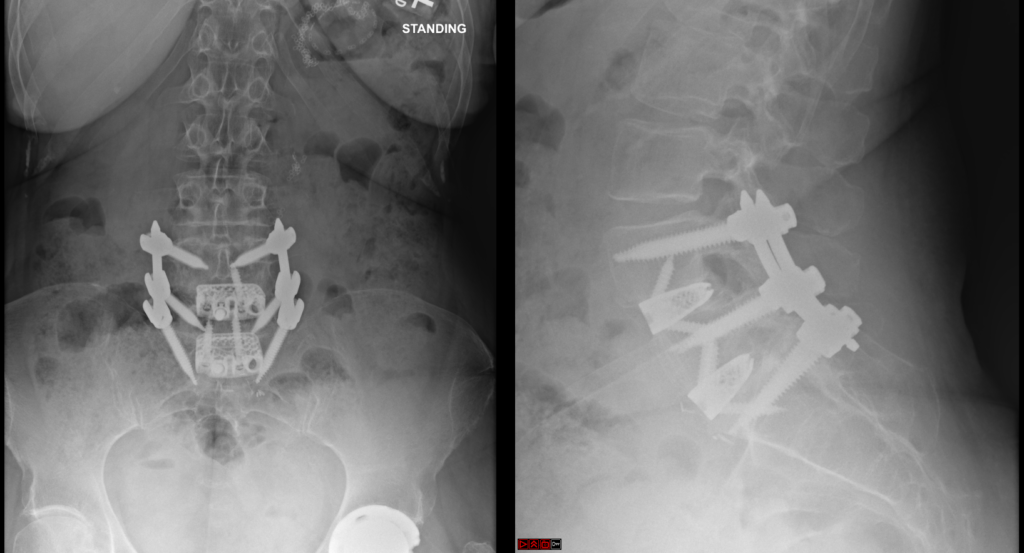

Anterior Lumbar Interbody Fusion